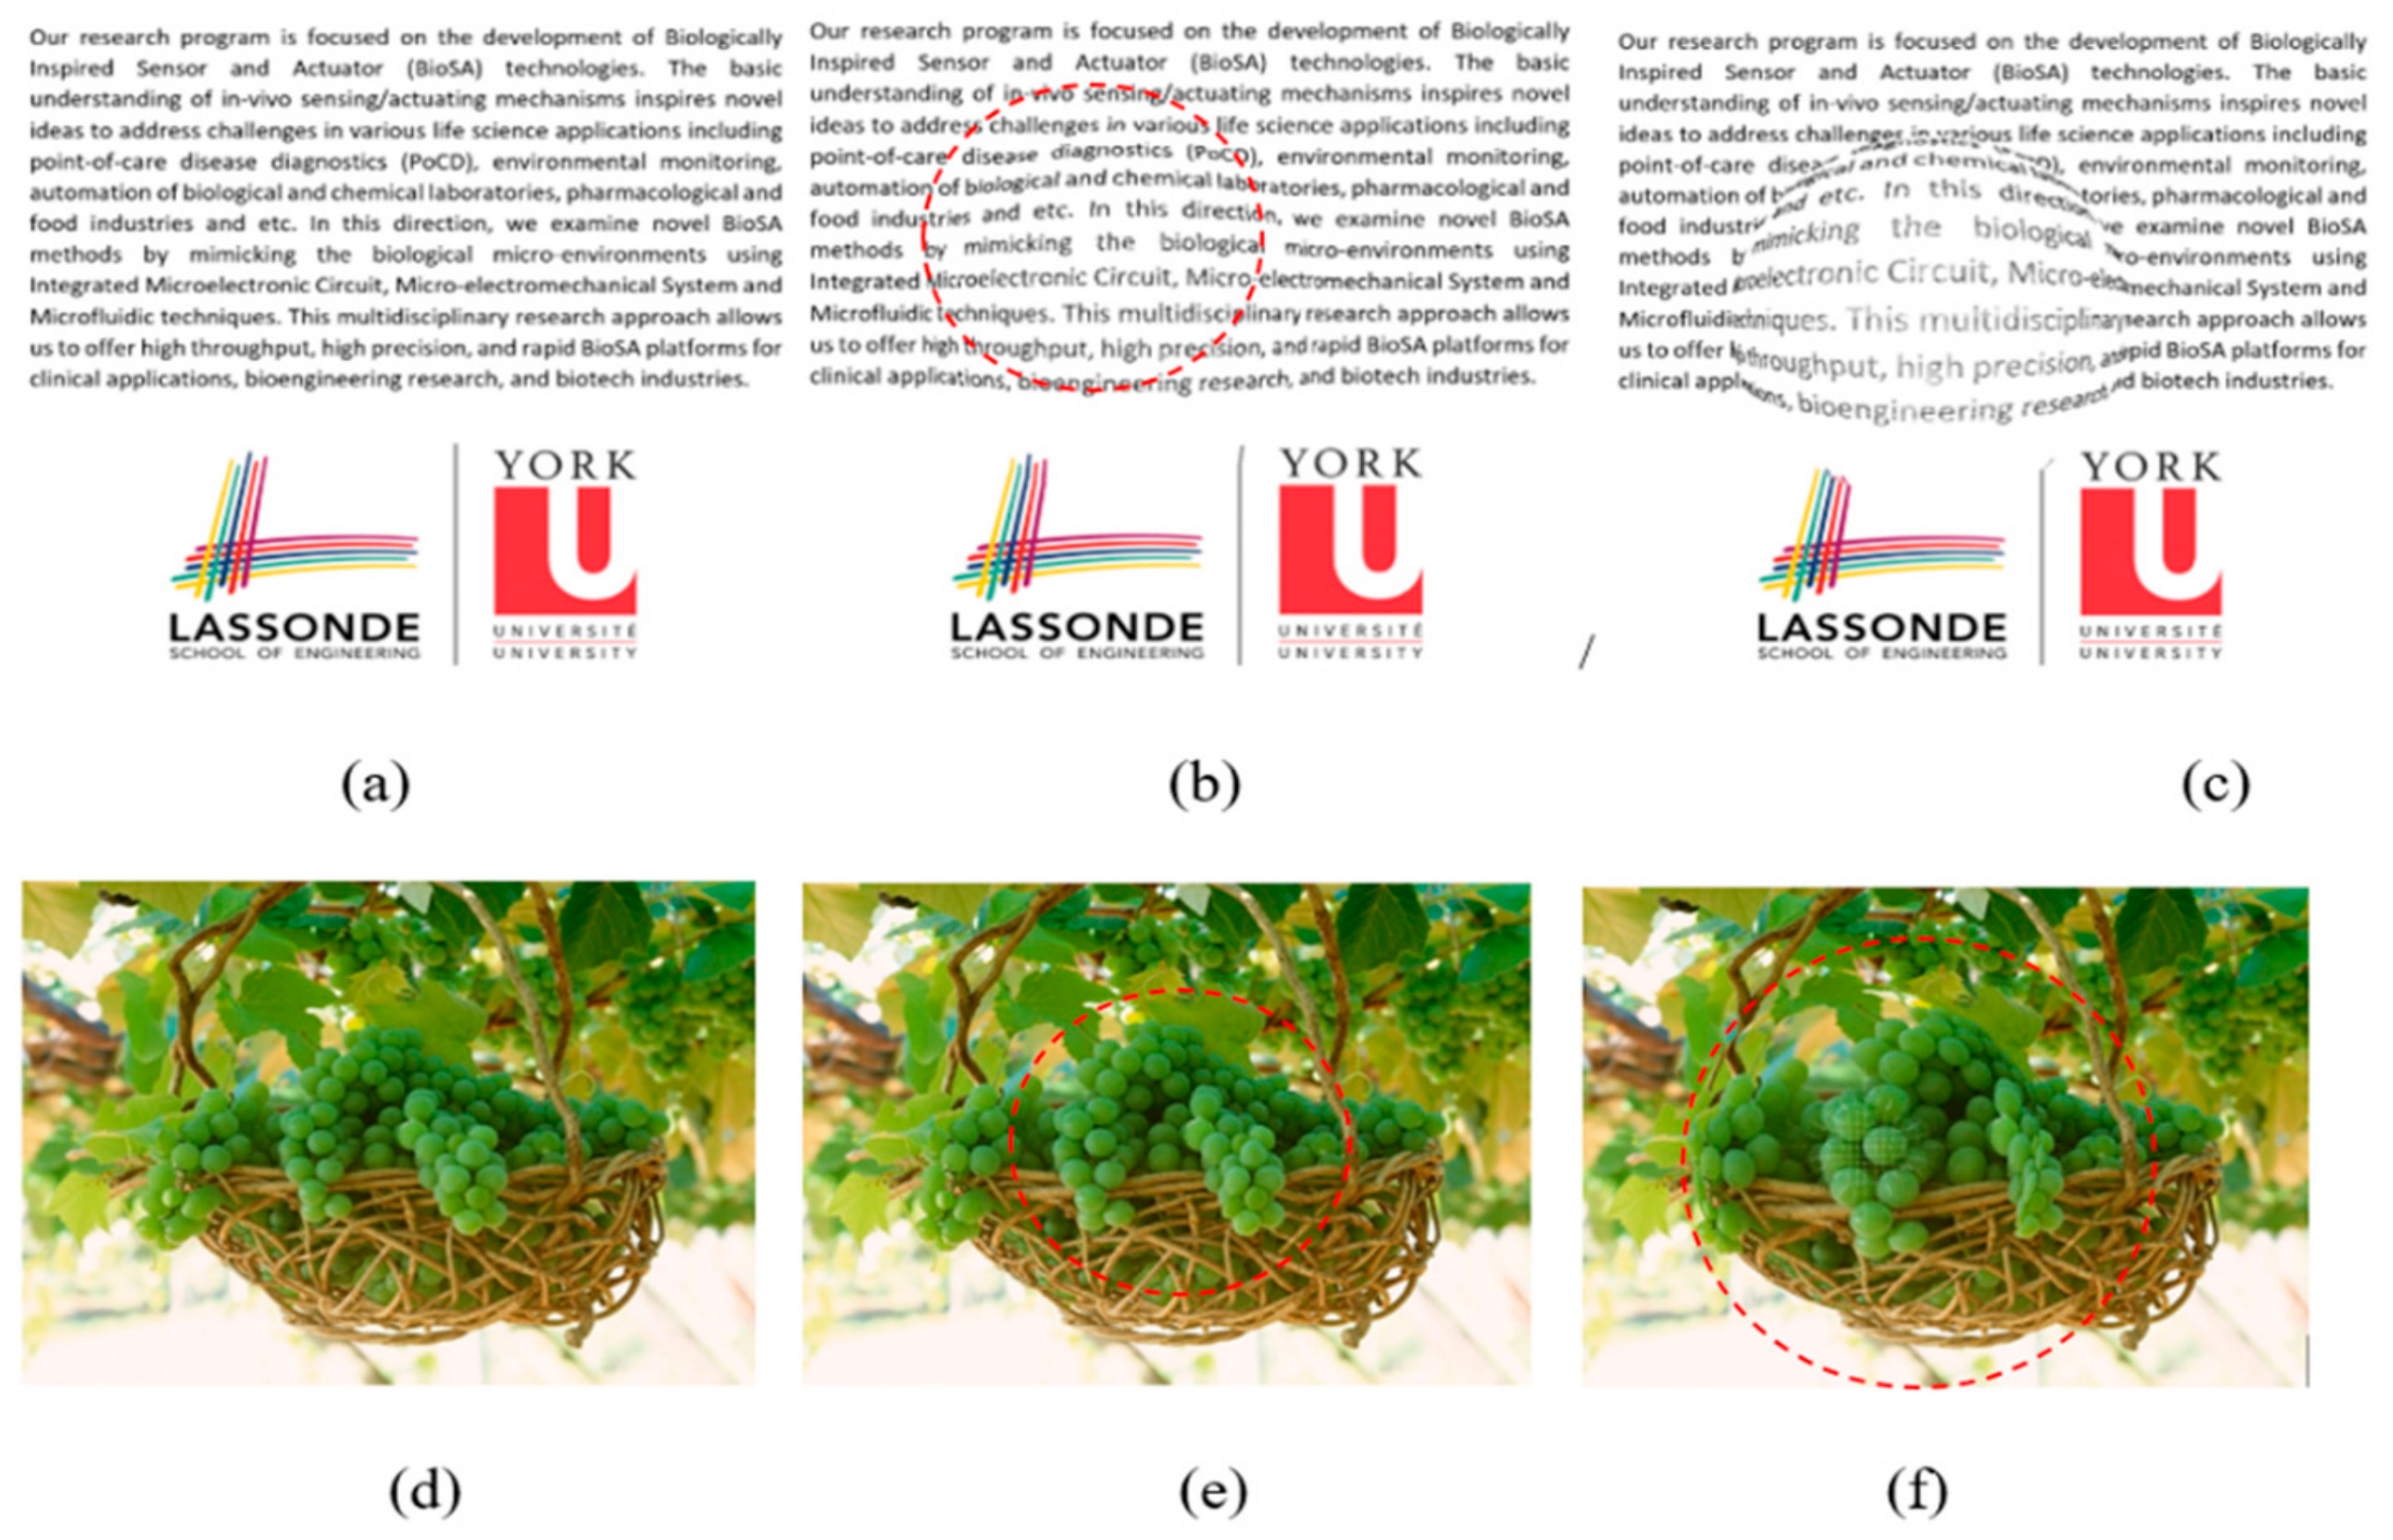

5.2. Visual Distortion Test

5.3. Estimation of Visual Distortion